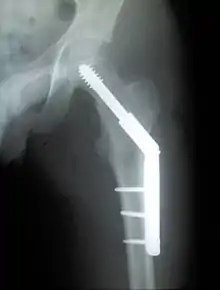

Fracture treated with cannulated screws

For low-grade fractures (Garden types 1 and 2), standard treatment is fixation of the fracture in situ with screws or a sliding screw/plate device. This treatment can also be offered for displaced fractures after the fracture has been reduced.

Fractures managed by closed reduction can possibly be treated by percutaneously inserted screws.[37]

Trochanteric fracture

Fracture supported by dynamic hip screw

A trochanteric fracture, below the neck of the femur, has a good chance of healing.

Closed reduction may not be satisfactory and open reduction then becomes necessary.[42] The use of open reduction has been reported as 8-13% among pertrochanteric fractures, and 52% among intertrochanteric fractures.[43] Both intertrochanteric and pertrochanteric fractures may be treated by a dynamic hip screw and plate, or an intramedullary rod.[42]

The fracture typically takes 3–6 months to heal. As it is only common in elderly, removal of the dynamic hip screw is usually not recommended to avoid unnecessary risk of second operation and the increased risk of re-fracture after implant removal. The most common cause for hip fractures in the elderly is osteoporosis; if this is the case, treatment of the osteoporosis can well reduce the risk of further fracture. Only young patients tend to consider having it removed; the implant may function as a stress riser, increasing the risk of a break if another accident occurs.